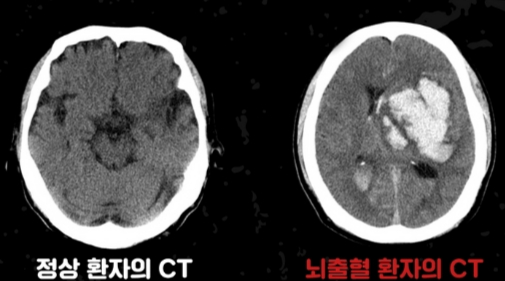

뇌에 갑작스럽게 타격이 가해지는 질환이 뇌졸중이다. 뇌졸중은 △뇌혈관이 막히는 '뇌경색' △혈관이 터지는 '뇌출혈'(출혈성 뇌졸중)로 나뉜다. 이 가운데 뇌출혈은 전체 뇌졸중의 약 20%를 차지한다.

뇌출혈은 전조 증상 없이 갑작스럽게 찾아오고 예후가 매우 나쁘다. 한번 발병하면 치료하더라도 후유증을 남길 수 있다. 빠른 인지·대처가 생명과 후유증을 좌우한다. 가천대 길병원 신경외과 김명진 교수는 "뇌출혈은 발병 즉시 치료해야 후유증을 남기지 않는다"고 설명했다.